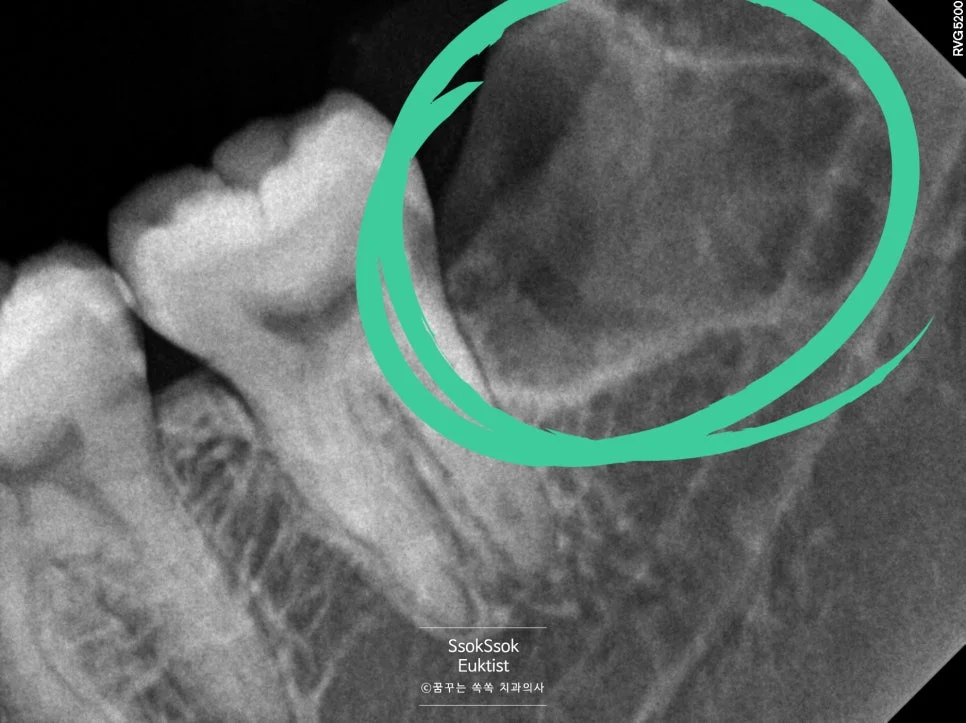

역시나 아래쪽 뿌리 일부가 남게 된 상태

사랑니 뿌리가 남았는데 괜찮을까?

역시나 아래쪽 뿌리 일부가 남게 되었는데요. 여기서 두 가지 선택지가 있습니다.

선택 1. 무리해서 뿌리 끝까지 제거

잘 접근이 되지 않고 깊은 부분에 무리한 기구 조작은 신경 손상 가능성이 있습니다🚫

선택 2. 그대로 두고 자연 치유 유도

거의 대부분 문제없이 치유됩니다.

1) 뼈의 일부로 둘러싸이거나

2) 조금씩 움직여 올라오면 쉽게 제거하면 됩니다.

이 경우 신경 손상 위험을 피하고 안전하게 두는 방법을 선택했습니다. 실제로 이런 경우 작은 뿌리 조각은 자연스럽게 흡수되거나 별다른 문제 없이 치유되는 경우가 많으니, 굳이 무리해서 제거할 필요는 없겠죠^^